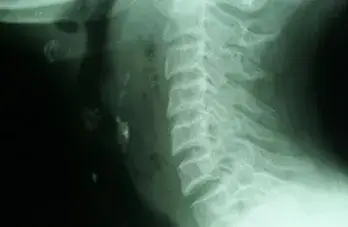

Barium Swallow

Bleeding Polypus Nose

Chicken Bone Nasopharynx

Conductive HL Audiogram

Endoscopic Ear Visualisation

Large Central Perforation

Mastoidectomy

Oropharyngeal Rhinosporidiosis

Tonsillitis

Fb Cricopharynx

Haller Cell

Inverted Papilloma Nose

Mastoidectomy 2

Mastoidectomy Cavity

Nasal Rhinosporidiosis

Neck Abscess

Palatal Ulcer

Retropharyngeal Abscess